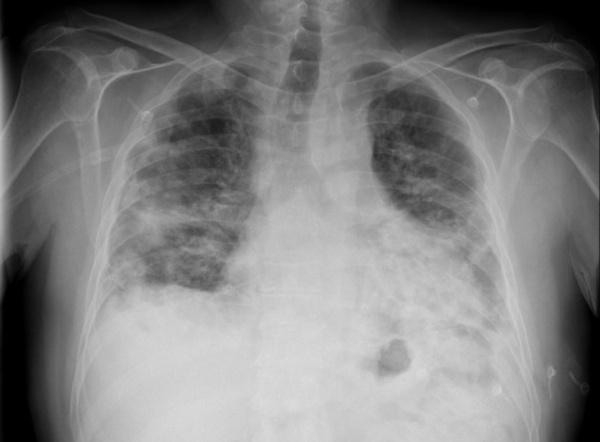

При рентгенографии органов грудной клетки выявляются двусторонние диффузные периферические альвеолярные затемнения при нормальных объемах легких; могут также встречаться периферические затемнения, характерные для хронической эозинофильной пневмонии Хроническая эозинофильная пневмония Хроническая эозинофильная пневмония (ХЭП) – заболевание неизвестной этиологии, которое характеризуется хроническим патологическим накоплением эозинофилов в легком. (См. также Обзор эозинофильных. Прочитайте дополнительные сведения . В редких случаях альвеолярные затемнения носят односторонний характер. Часто наблюдаются рецидивирующие и мигрирующие инфильтраты. В редких случаях в начале заболевания могут наблюдаться нерегулярные линейные или очаговые интерстициальные инфильтраты или «сотовое легкое».

При КТВР выявляется очаговая консолидация воздушных пространств (у 90% пациентов), затемнения по типу «матового стекла», узловые затемнения, утолщение стенок и расширение бронхов. Очаговые затемнения встречаются чаще в периферических отделах нижних долей легких. КТВР позволяет обнаружить более обширные зоны поражения, нежели ожидается по результатам рентгенографии органов грудной клетки.

Рис 1. Рентгеновская компьютерная томография 08.07.10. Аксиальная проекция.

Рентгенологическая симптоматика имеет особенности:

- Двусторонний процесс. Описаны солитарные инфильтраты КОП, однако в целом они встречаются довольно редко [2].

- Субплевральная локализация.

- Зоны консолидации высокой плотности, определяющиеся в режиме «Chest».

- Одновременно с зонами консолидации присутствуют «лоскутные» участки «матового» стекла (рис. 8) - важный симптом, описанный впервые G.R. Epler, имеющий место у 80% пациентов [3].

- Зоны поражения могут менять свою локализацию и плотность, "мигрировать" с одного места на другое, если не проводится стероидная терапия (такой симптом характерен также для хронической эозинофильной пневмонии).

Рис. 8. Компьютерная томография органов грудной клетки при КОП. Аксиальная проекция.

а, б - субплеврапьно расположенные участки неоднородного уплотнения легочной ткани с четкими границами, с тракционно расширенными бронхами.

в-г - участки консолидации легочной ткани чередуются с участками уплотнения легочной ткани по типу "матового стекла".

По статистике на КТ в 90% случаев определяются субплевральные и перибронхиальные уплотнения легочной ткани, чаще в нижних долях легких. У 60% больных имеются участки «матового стекла». Уменьшение степени выраженности "матового стекла" при динамическом наблюдении свидетельствует об эффективности проводимой терапии.